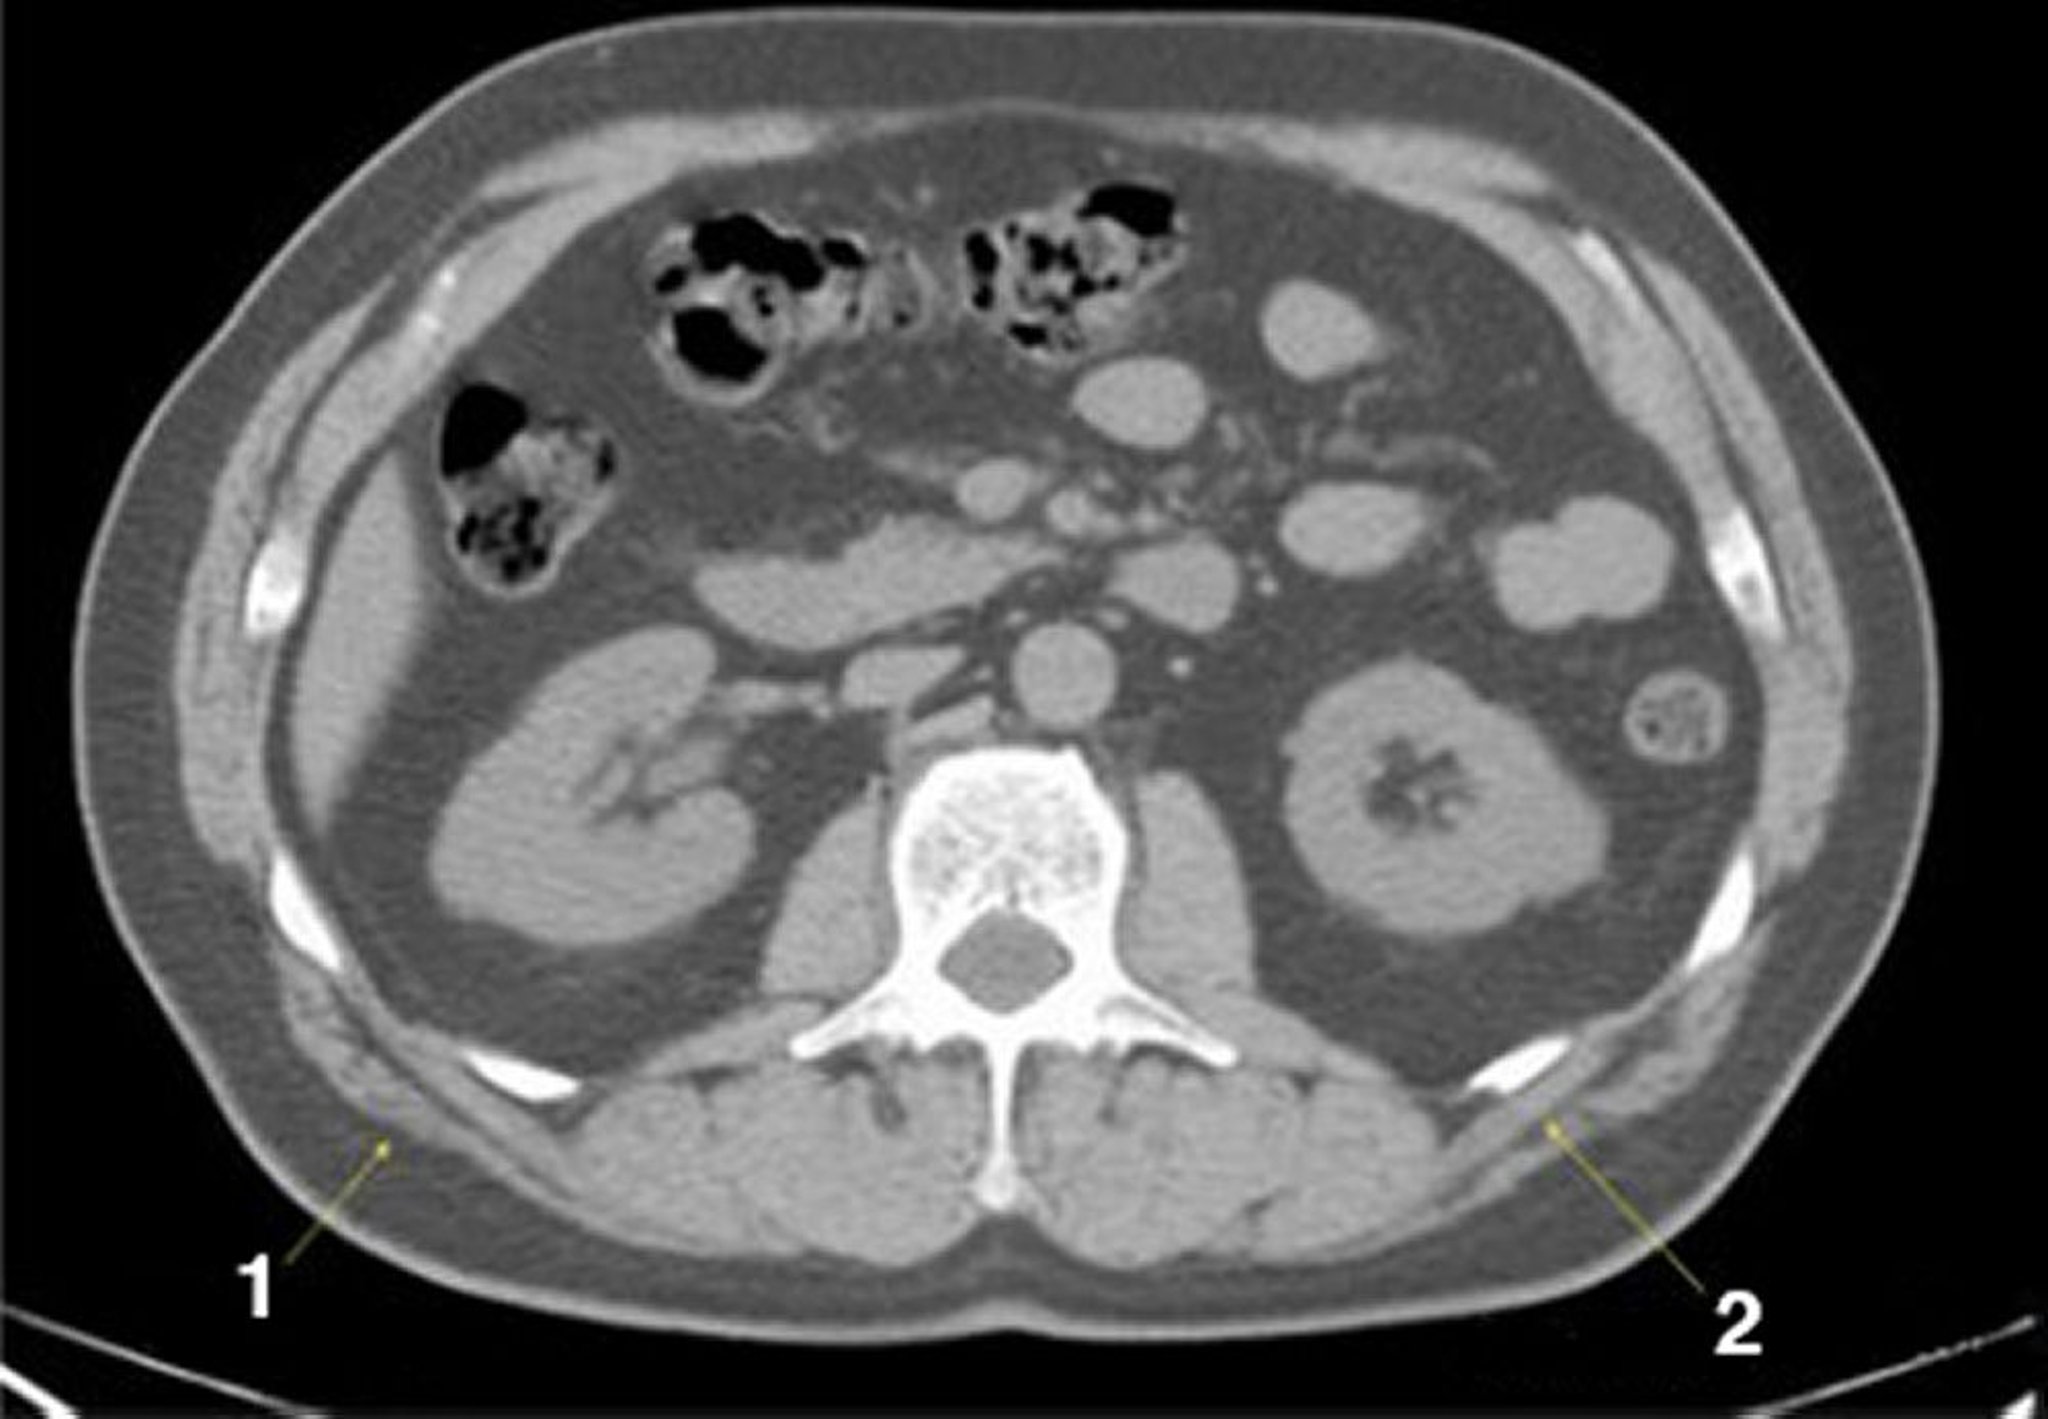

TDM sans contraste de l'abdomen et du bassin montrant une anatomie normale (diapositive 15)

1 = latissimus dorsi; 2 = serratus posterior.